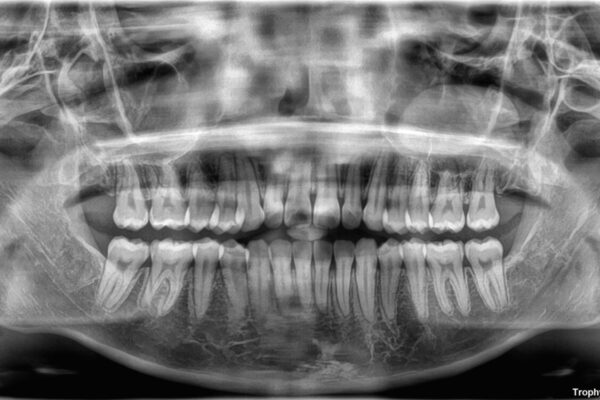

前歯のデコボコが気になるでのことで来院された患者様です。

歯列アーチが狭くスペース不足により前歯がデコボコしている状態でした。見た目を改善しつつ、前歯を前方に突出させず、自然な笑顔を目指したいというご希望でした。

・アーチを側方に拡大して歯が並ぶスペースを確保

・抜歯は避け、非抜歯での対応

・目立ちにくい審美装置による矯正